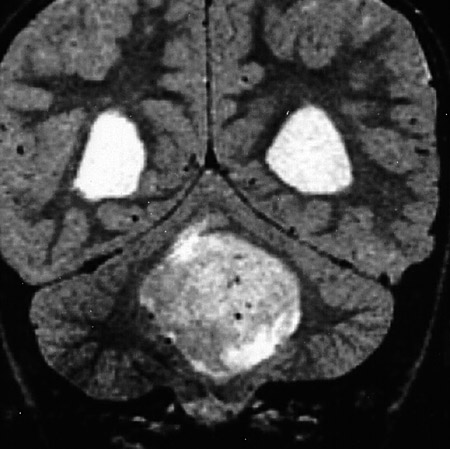

| The coronal T2 weighted MRI scan above and the enhanced MRI scan in axial view below both reveal a medulloblastoma of the cerebellar vermis in a child. Obstruction to CSF flow in the fourth ventricle may lead to hydrocephalus. Destruction of cerebellar tissue may be manifested by ataxia in the patient. |